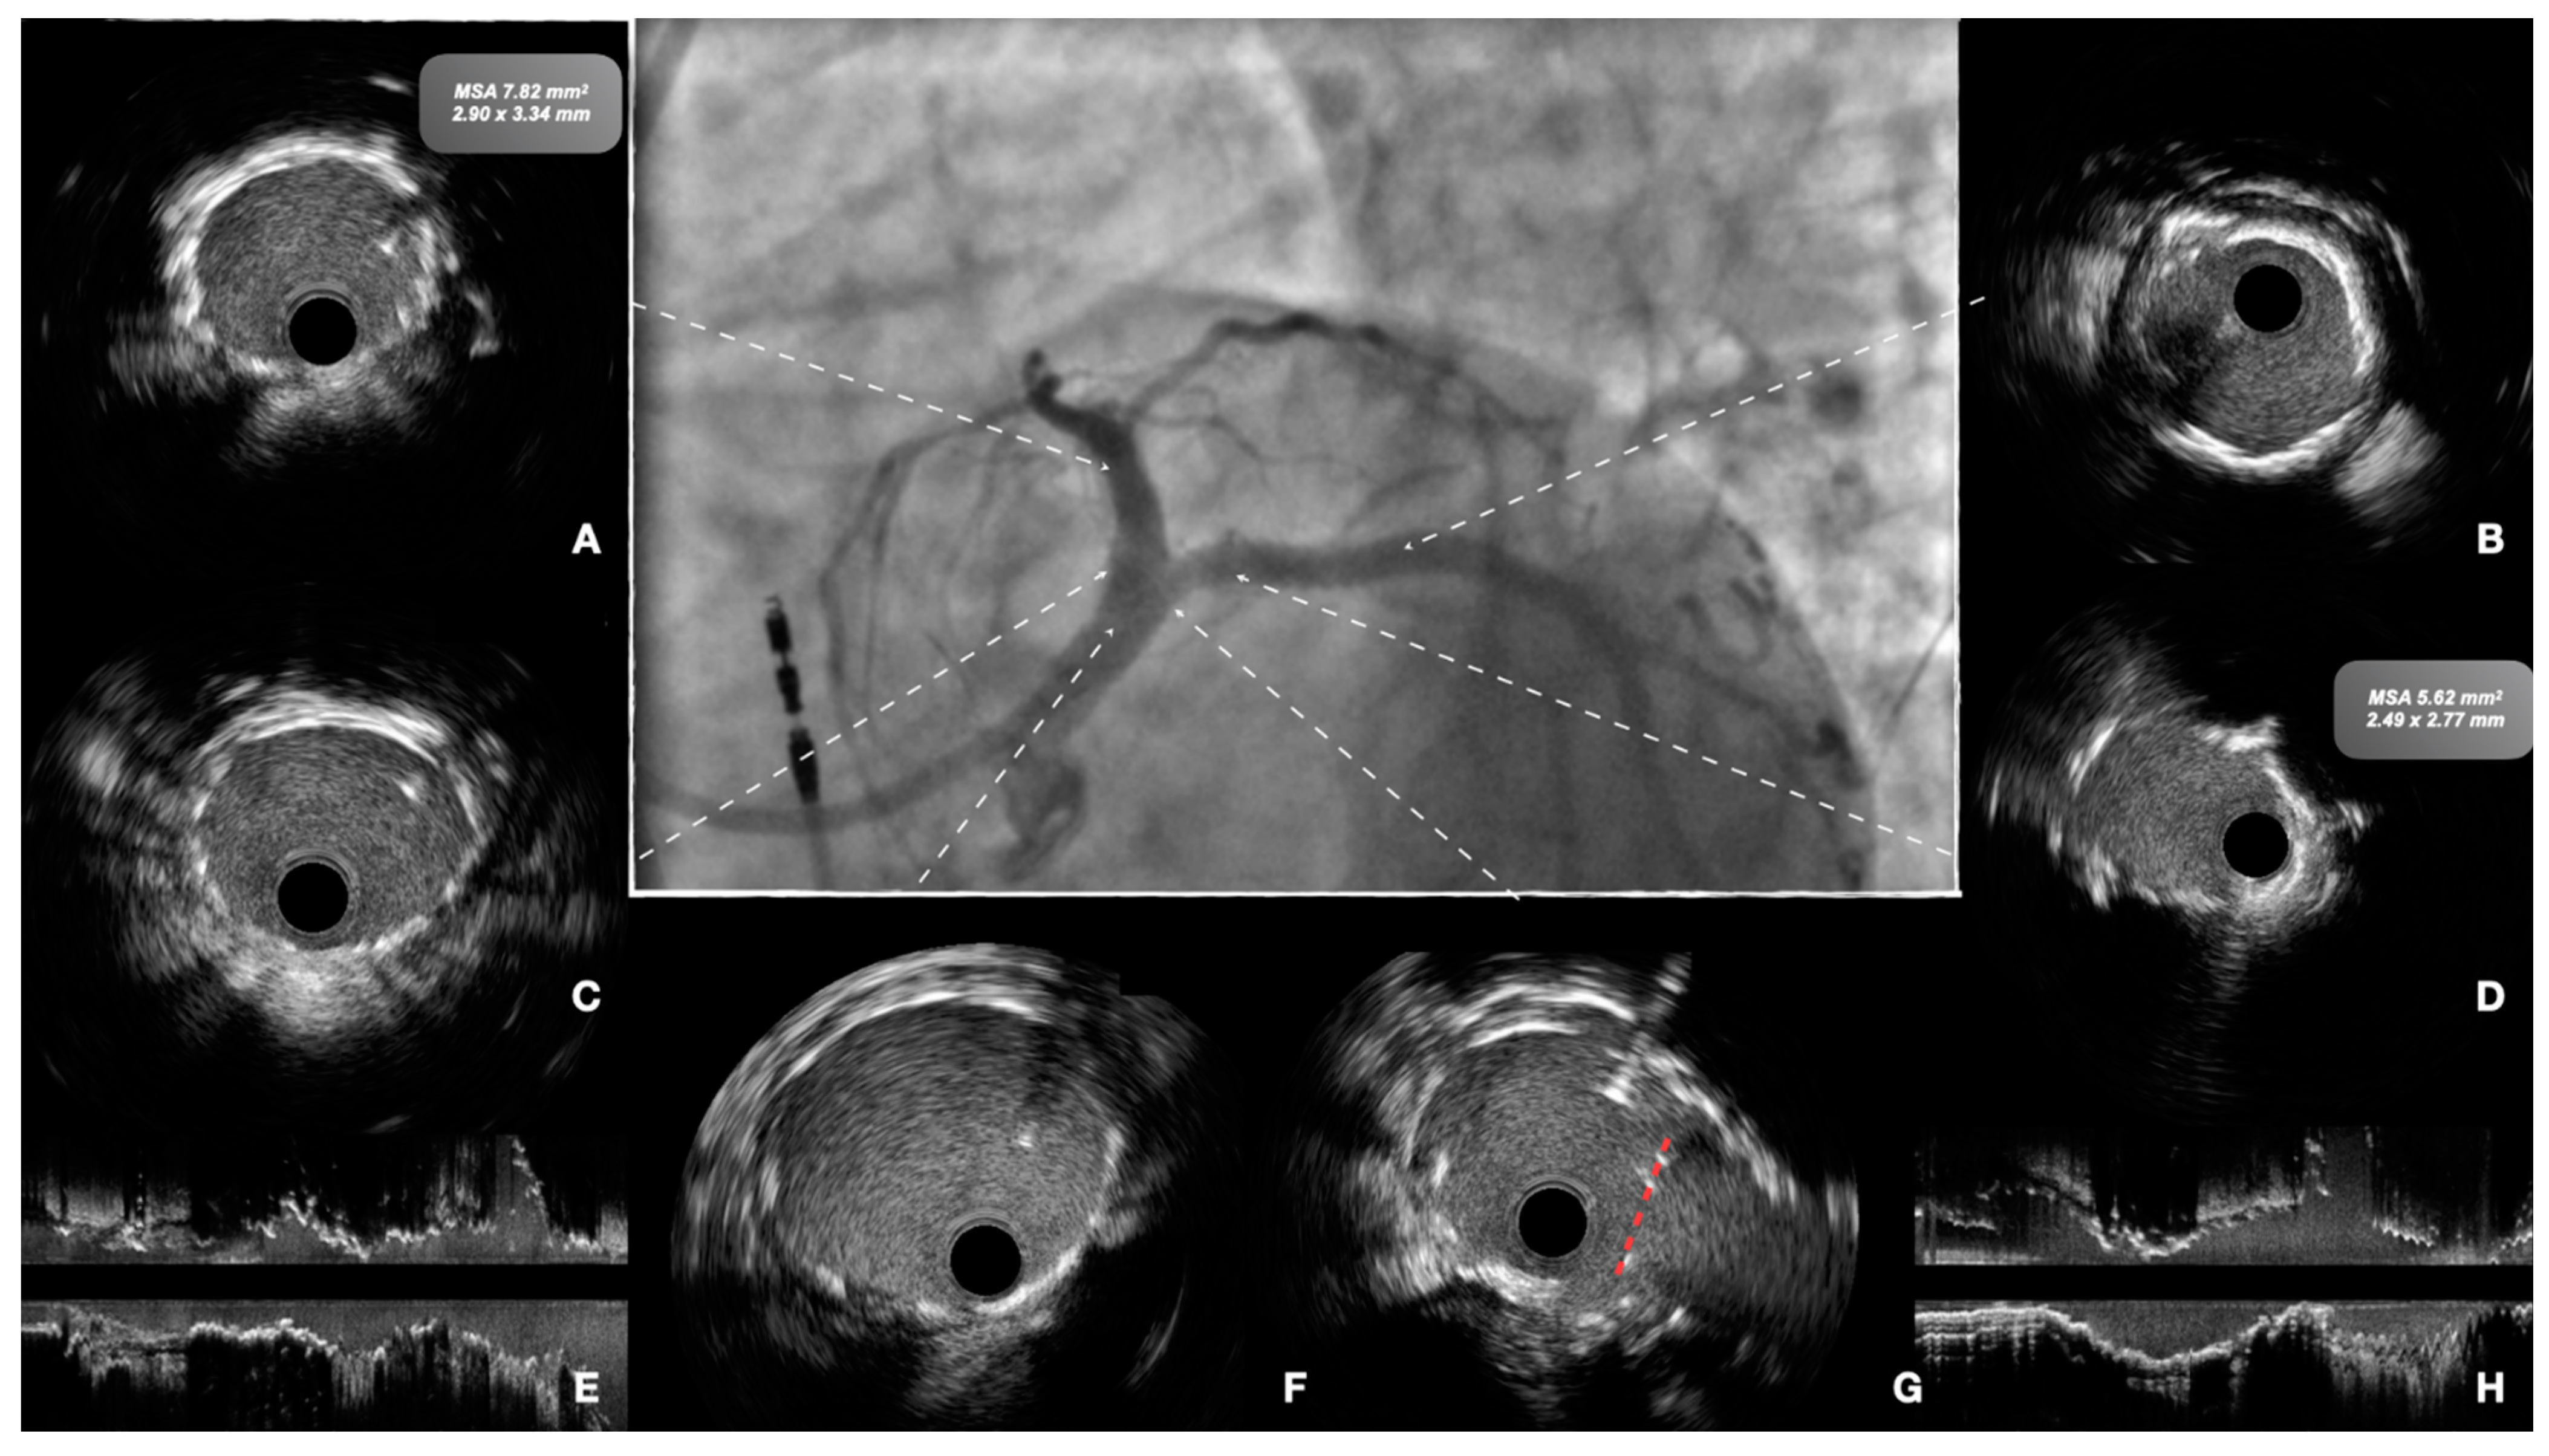

7. Technical Considerations during PCI

8. Intracoronary Imaging Guidance before, during and after PCI